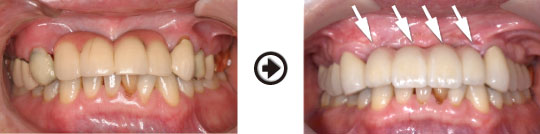

インプラント治療(GBRと併用)症例

骨が少ない場合は、厚みや高さを増大(GBR)させた、しっかりとした骨の中に、 インプラントを理想的な位置に植立することがインプラントを長持ちさせる為には、重要です。

骨幅が無い所でも骨造成することでインプラント治療が可能になります。